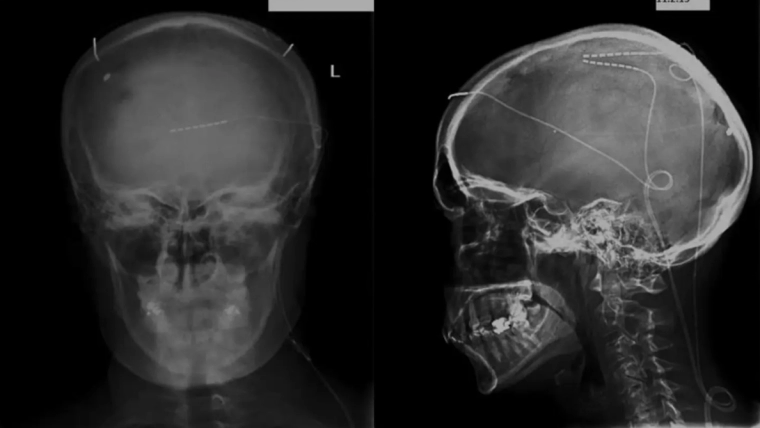

Μία πρωτοποριακή επέμβαση τοποθέτησης ηλεκτροδίων στον εγκέφαλο, που έγινε στο νοσοκομείο “Ευαγγελισμός”, άλλαξε σημαντικά την ποιότητα ζωής ενός νέου ανθρώπου που πάσχει από μία δύσκολη νευροεκφυλιστική νόσο και δεν μπορούσε να αυτοεξυπηρετηθεί. Με τα ηλεκτρόδια ο ασθενής βελτίωσε τη λειτουργία των νεύρων του, ενώ υπήρξε καλύτερος έλεγχος των συμπτωμάτων.

“Στις αταξίες παρεγκεφαλιδικής εκφυλιστικης αιτιολογίας, δεν υπάρχει προς το παρόν αποκατάσταση. Τμηματα της παρεγκεφαλιδας και του εγκεφαλικού φλοιού συμμετέχουν στο παθολογικο κύκλωμα στην αταξία. Δημιουργώντας ηλεκτρικό πεδίο με υποδόρια ηλεκτρόδια, διεγειραμε τις παραπάνω δομές.

Με αυτό τον τρόπο πετύχαμε σημαντική ανταπόκριση των συμπτωμάτων. επίσης, σημαντικό είναι πως η κλινική εικόνα του ασθενούς συνεχίζει να βελτιώνεται στον χρόνο.”